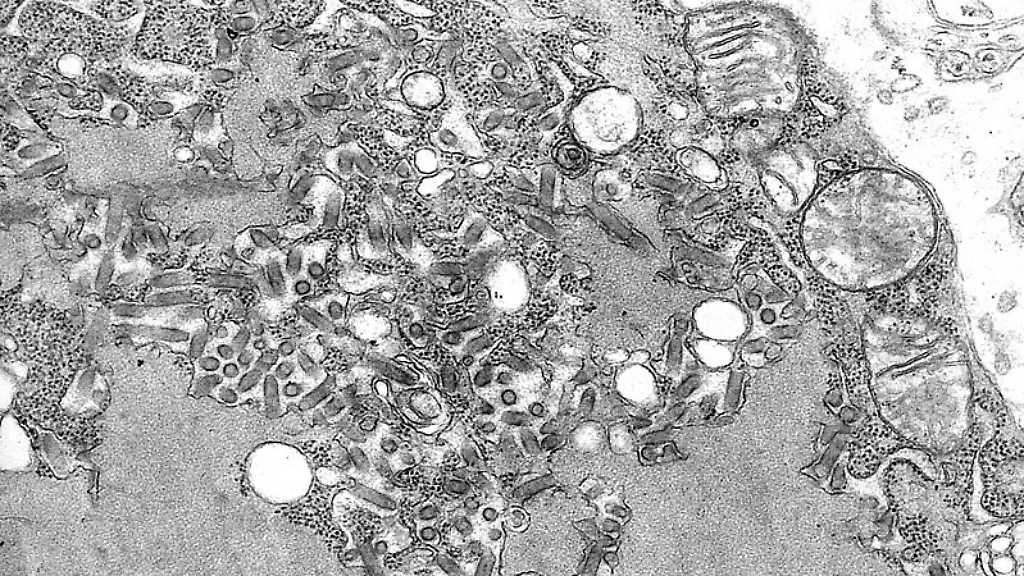

Tollwut ist eine tödliche Viruserkrankung, die durch Kontakt mit Speichel oder Blut infizierter Tiere auf den Menschen übertragen werden kann. Mit fortschreitender Krankheit verschlimmert sich der Schweregrad von grippeähnlichen Symptomen bis hin zu Halluzinationen und Schluckbeschwerden. Wenn man von einem potenziell tollwütigen Tier gebissen wird, hilft eine Impfung. Die sollte aber umgehend erfolgen. Denn treten erste Symptome auf, verläuft die Krankheit fast immer tödlich.